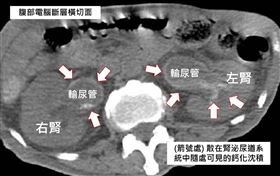

結石滿滿覆蓋泌尿道!男急性腎臟功能惡化

泌尿道結石很常見,結石通常是顆粒狀,竟有人的結石是滿...